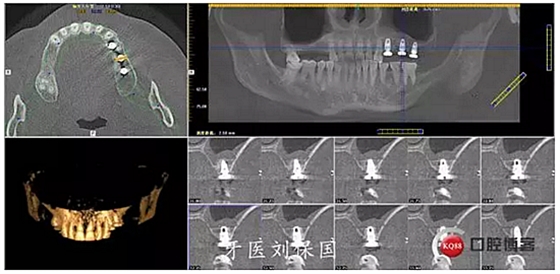

4.六個(gè)月后二期CT: